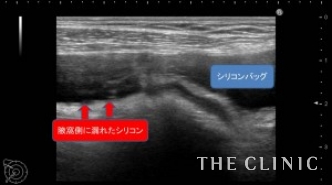

この方は、20年前に大胸筋下へバッグを挿入されています。今回、乳がん検診にてバッグの破損と被膜の石灰化を指摘され、バッグ抜去をご希望でご来院されました。エコーにて、両側のバッグ破損と被膜の石灰化を認めます。右側は脇の近くまでシリコンが漏れ出ている状態でした。

左側は被膜内での漏れであったため脇から手術を行い、スムーズに抜去し洗浄を行いました。右側はエコーの通り、シリコンが脇のほうまで漏れている状態であったため、バスト下部と脇からの手術を行い、漏れ出ていたシリコンを全て取り出して洗浄を行いました。